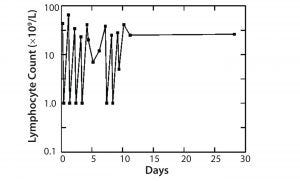

Figure 1: Treatment of leukemia with Campath-1M

The first MAb, Campath-1 IgM antibody, depleted T-cells in the blood of a patient with leukemia to <1% of starting level. Although those cells returned the next day, we could show that the treatment was fairly safe, that T-cells could be attacked, and that complement could be activated. When the same treatment was conducted with bone marrow, we found >99% of T-cells were removed from the bone marrow. When patients who needed the transplant with this bone marrow were infused, their instance of GVHD was greatly reduced (Figure 1).